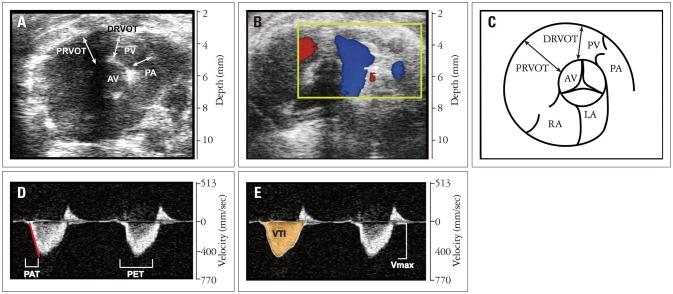

Right heart echocardiography evaluations of CD1 and C57BL/6 mice were performed under 1-3% isoflurane anesthesia using Vevo® 2100 Imaging System with a high-frequency (18-38 MHz) probe (VisualSonics MS400). We have provided a practical guide on how to image and assess the right heart of a mouse which is frequently used to evaluate development of right heart failure due to pulmonary hypertension.

Our results show significant differences between CD1 and C57BL/6 mice. Right ventricle structural assessment showed significantly larger ( < 0.05) size, and pulmonary artery diameter in CD1 mice (n = 11) compared to C57BL/6 mice (n = 15). Right heart systolic and diastolic functions were similar for both strains.